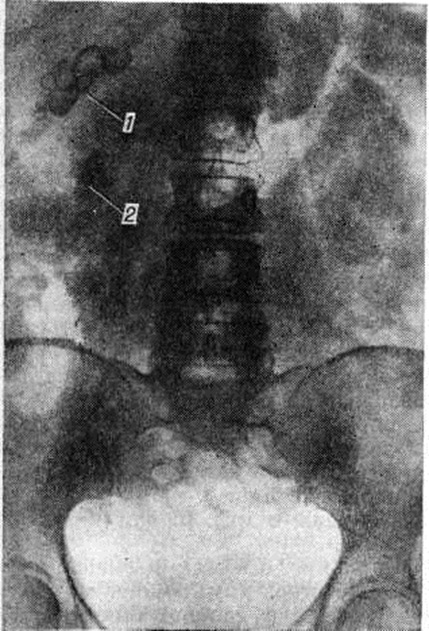

Рентгенологические метод является основным в диагностике Почечнокаменная болезнь Он позволяет выявить не только наличие камней, но и установить их форму, величину, локализацию, структуру, а также получить представление об изменениях в анатомо-функциональном состоянии почек и мочевых путей. Исследование начинают с обзорной рентгенографии брюшной полости, начиная от ThXl до лонного сочленения. Обнаружение на обзорной рентгенограмме тени, подозрительной на конкремент, не требует дифференциальной диагностики только в случае коралловидного камня, являющегося слепком чашечно-лоханочной системы (рисунок 2). Камни почечных чашечек представляют собой их слепки или имеют неправильную, округлую форму; камни почечной лоханки часто округлые или треугольные; камни мочеточника — цилиндрической, веретенообразной или неправильной формы. При аномалиях мочевых путей конкремент может находиться вне обычной локализации почек и других органов мочеполовой системы. Обнаружение камня на снимке зависит от его размеров, химический состава и локализации. Наиболее интенсивное изображение дают оксалаты, затем камни смешанного состава и фосфаты. Оксалаты имеют шиповидные, фестончатые контуры и напоминают тутовую ягоду. Коралловидные камни чаще всего компактны, но могут быть слоистыми, как и остальные конкременты смешанного состава, иногда они достигают гигантских размеров. Слоистое строение камней на рентгенограммах обусловлено различной проницаемостью для рентгеновского излучения составляющих их солей. Около 10% камней с низким атомным весом (ураты, белковые, цистиновые и ксантиновые камни) не видны или дают неотчётливую тень. Особенно трудно выявить камни, проецирующиеся на костный скелет (ребра, поперечные отростки позвонков, крестцово-подвздошные сочленения). Для их обнаружения производят прицельные снимки в косых и атипичных проекциях, томо или зонографию. Томография (смотри полный свод знаний), применяемая самостоятельно или в сочетании с контрастными исследованиями, показана при недостаточной подготовке больного к рентгенологическое исследованиям, почечной колике, сопровождающейся парезом кишечника, или при малых размерах камней. Поскольку при Почечнокаменная болезнь довольно часто конкременты самопроизвольно отходят из чашечно-лоханочной системы, они могут проецироваться по ходу мочеточника паравертебрально, имеют тенденцию задерживаться над одним из его анатомических сужений. Наиболее важные сведения о принадлежности выявленной тени к мочевым путям, о локализации камня, вызванных им нарушениях функции почек, уродинамики, анатомического состояния мочевых путей (гидрокаликоз, пиелэктазия, гидроуретеронефроз — расширение чашечек, лоханки, мочеточника и почки) выявляются при экскреторной урографии (рисунок 3, б) с предварительной обзорной рентгенографией (рисунок 3, а). Она позволяет установить вид лоханки (открытая или закрытая, внутрипочечная или внепочечная), состояние лоханочно-мочеточникового сегмента (смотри полный свод знаний: Пиелография). Обычно рентгенопозитивный конкремент определяется в мочевых путях, но иногда его изображение перекрывается, как бы тонет на фоне контрастированной мочи, особенно при небольшом камне или малой интенсивности его изображения. При рентгенонегативных камнях виден дефект наполнения мочевых путей (в том числе и лоханки) с чёткими контурами (рисунок 4). В отличие от опухоли лоханки в косых проекциях вокруг камня сохраняется ободок контрастного вещества. Обычно при камнях лоханки, достигающих в диаметре 3 сантиметров и более, наблюдаются пиелэктазия и гидрокаликоз. Произведённые в процессе экскреторной урографии телевизионная пиелоуретероскопия в сочетании с кинематографией или видеомагнитофонной записью изображения позволяют оценить нарушения тонуса и моторной функции верхних мочевых путей при камнях, отличить спастические, функциональный процессы от органических. Если спустившийся в мочеточник камень частично закрывает его, то отмечаются расширение мочеточника и лоханки (пиелоуретерэктазия) выше уровня расположения конкремента. На экскреторных урограммах, произведённых во время почечной колики, выявляется увеличенная почка с усиленным нефрографическим эффектом без контрастирования чашечно-лоханочной системы и мочеточника — так называемый большая белая почка. Такая рентгенологическое картина указывает, что функция почки сохранена. При длительной полной блокаде камнем (более 3—4 недель) функция почки из-за атрофии снижается и может полностью утрачиваться. На экскреторных урограммах, произведённых после почечной колики, иногда наблюдается проникновение контрастированной мочи за пределы мочевых путей, а также лоханочно-почечный рефлюкс. Ретроградную пиелоуретерографию с жидким контрастным веществом или кислородом производят только при значительном снижении функции почек, при сомнении в диагнозе, особенно в тех случаях, когда при экскреторной урографии не выявляется рентгенонегативный камень. Рентгенографию мочеточника после введения в него катетера производят в прямой и косой проекциях. Если при этом тень, подозрительная на камень, на обоих снимках находится рядом с катетером или сливается с его тенью, то диагноз Почечнокаменная болезнь не вызывает сомнений. Тень, не относящаяся к мочеточнику, определяется на некотором расстоянии от катетера. На ретроградных пиелограммах с жидким контрастным веществом небольшой концентрации рентгенонегативные камни выявляются в виде дефекта наполнения. Особенно демонстративными такие камни становятся при пневмопиелорентгенографии или пневмопиелотомографии (рисунок 5). С помощью ретроградной уретерографии удаётся выявить рентгенонегативный камень в мочеточнике, верхние границы дефекта при этом имеют вогнутую форму (рисунок 6).